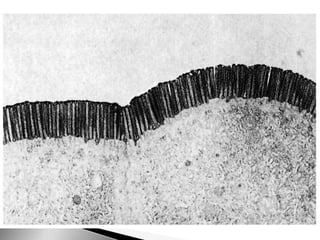

Histología - Tejido Epitelial